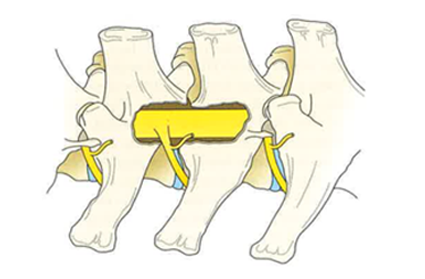

Een neurologisch onderzoek is ook noodzakelijk voorafgaand aan een MRI-onderzoek. Een MRI-onderzoek is tijdrovend, daarom is het essentieel om de juiste lichaamsregio van uw dier te scannen. Een voorafgaand neurologisch onderzoek helpt om de te scannen regio vast te leggen. Bovendien kunnen we zo de ernst inschatten van de MRI-afwijkingen die we vaststellen op de scan.

Uiteraard is het eveneens mogelijk dat uw dierenarts op basis van voldoende eigen neurologische ervaring, u en uw dier rechtstreeks doorstuurt voor een MRI-scan.